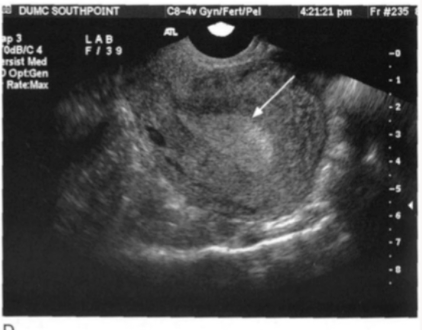

When assessing the endometrium the sonographer evaluates what three things:

1) thickness

2) echgenicity

3) contour (should be homogenous)